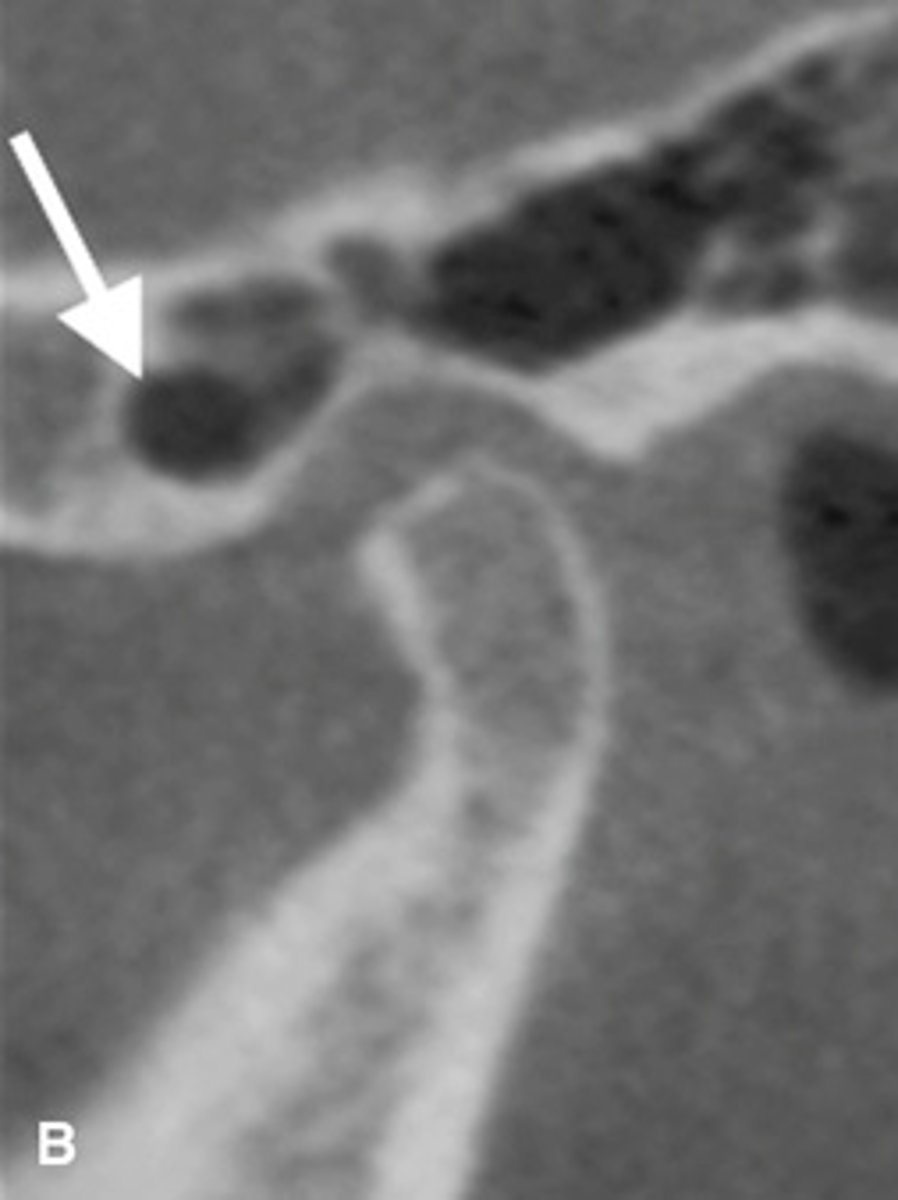

Bifid condyle

- Vertical depression in the condylar head

- often unilateral but may be bilateral

- may be a result of trauma

- some patients may have TMJ dysfunction

- Treatment isn't indicated unless pain or fxn impairment.

What is this developmental abnormality, and what is the etiology for it?